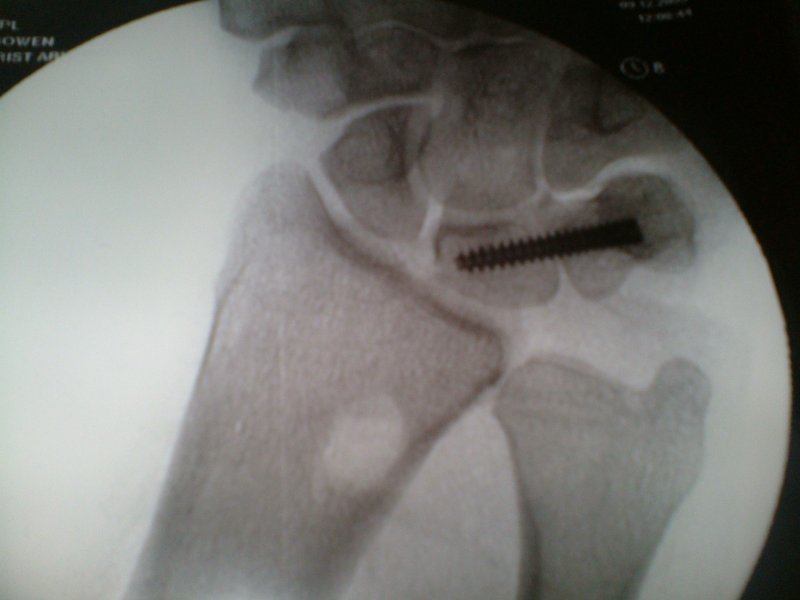

Latest Wafer Procedure

Wrist Before the Shortening